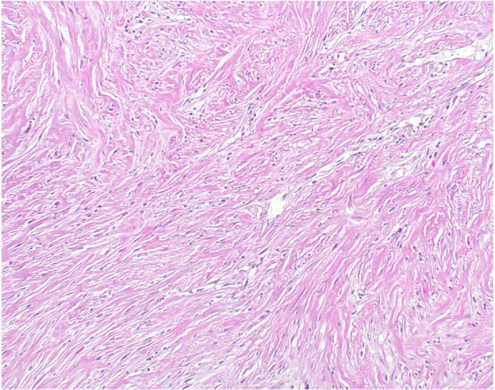

線維形成型中皮腫(desmoplastic mesothelioma)の病理像(HE染色)

膠原線維が束状配列や花むしろ様配列を呈して増生し、その中に紡錘形細胞をみる。細胞密度が低く、細胞異型も乏しいので、良性の線維性胸膜炎との鑑別に注意が必要である。